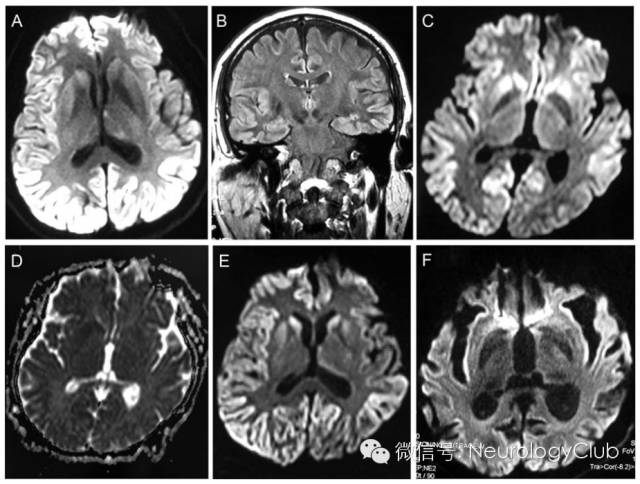

42岁独自生活的男性职员,既往有高血压病史,但控制良好,因“进行性记忆障碍5月”就诊。患者表现为易激惹,且难以回忆起最近的谈话。四肢有麻木和刺痛感,行动缓慢,思睡。起病后3月患者至另一家医院行头颅MRI检查,提示明显的皮层相对对称的DWI高信号,病灶无强化(图,A-B)。脑电图提示全脑慢活动。尽管脑脊液14-3-3蛋白水平正常,但临床症状结合MRI初步考虑CJD,因患者PRNP基因无突变,因此散发型的可能性大。患者接受静脉注射甲强龙,500mg/d,共7天后改口服激素,逐渐减量。

患者症状无改善,在来我院(2012年3月)前1周病情加重。神经系统查体提示明显的认知功能缺损和锥体外系体征。简易精神状态检查量表评分20(总分30)。患者双侧对称性运动迟缓,上肢齿轮样强直,指鼻试验不准。再行MRI提示尾状核、额叶、颞叶和枕叶皮层DWI高信号,ADC低信号(图,C-D)。肌电图提示四肢感觉波幅明显下降。

(图:A-B:起病3月时的DWI和FLAIR可见明显的较为对称的双侧皮层灰质受累;C-D:起病5月时皮层下灰质(尾状核)及皮层灰质病灶DWI呈高信号,ADC呈低信号;E:螯合治疗后DWI上病灶无明显改善;F:2年随访时可见脑萎缩)

结缔组织疾病筛查试验,梅毒血清学及电压门控钾离子通道和副肿瘤抗体检测均无殊。重金属筛查发现患者血汞水平76.3nmol/L(呈波动性,与饮食摄入和其他急性暴露有关,无症状患者可能有比之更高的血汞浓度),尿汞水平109.2nmol/L(参考值:0.0-12.5nmol/L;尿汞水平的可靠性较高)。我们再次询问病史,患者起病前数天在床上打破了汞柱血压计,在第二天用小笤帚清理了溢出的汞。患者接受螯合剂2,3-二巯基丙磺酸钠治疗。麻木和刺痛感明显好转,记忆和运动症状只有轻度改善,复查头颅MRI未见变化(图,E)。出院后2年随访,患者存在持续性认知功能缺损和运动迟缓,血汞水平2.5nmol/L,尿汞水平5.5nmol/L,MRI上可见持久的脑损害(图,F)。